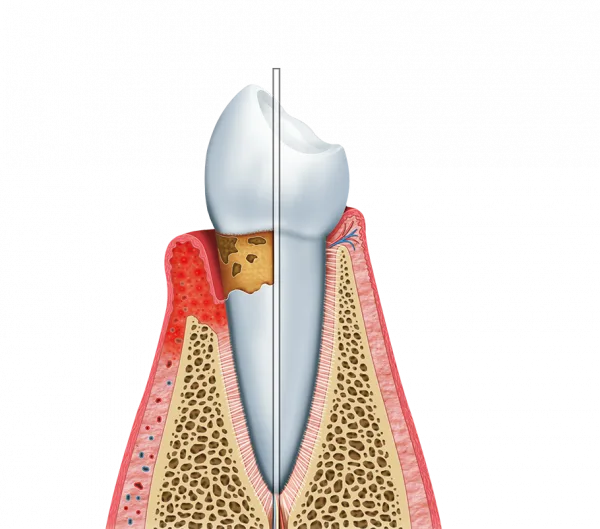

O tratamento de periodontite é crucial para a manutenção da saúde bucal.

O tratamento de periodontite ajuda a restaurar a saúde das gengivas e dos dentes.

Isso é alcançado por meio de procedimentos que removem a placa bacteriana e o tártaro.

- Redução do sangramento gengival.

- Eliminação do mau hálito persistente.

- Preservação dos dentes naturais.

Estudos indicam que a periodontite está ligada a várias doenças sistêmicas, como diabetes e doenças cardíacas.